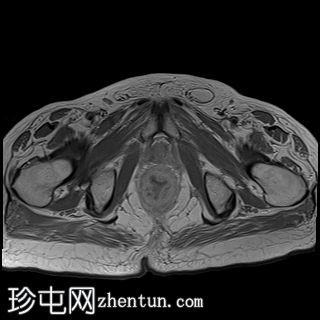

矢状位

T2加权像

直肠下三分之一处可见一段弥漫性不规则肠壁增厚,伴浆膜外延伸,在右前外侧壁形成“C”形肿块,增强后呈不均匀强化,中央可见坏死。

左侧外侧壁和后壁可见大片缺损,内含气体和粪便,被不规则增厚的肠壁包裹。该缺损在T1加权像上呈低信号,在T2加权像上呈高信号,并伴有明显的扩散受限。

可见肠系膜脂肪间隙条索状改变和水肿。